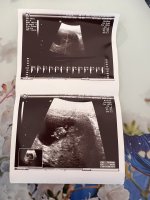

Merhaba hanımlar.. Ben yeni üye oldum.. Bi sorum var.. 13 haftalık Bi bebek cinsiyet tahmin edebilirmisiniz